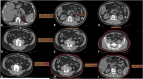

We previously developed and validated LAPDOCTOR (LAParoscopic-Donor-nephreCTomy-scORe), a novel scoring system for the preoperative assessment of the difficulty of living donor nephrectomy (LDN). To prove its significance, we extended our investigation to a prospective, multicenter, national study. Difficulty was assessed by the operating surgeon using a scale from 1 to 3 (1-standard, 2-moderately difficult, 3-very difficult) based on eight parameters: availability of laparoscopic space, mobilization of the colon, kidney, gonadal, adrenal and renal vein, renal artery, and ureter. Donor CT-scans were blindly reviewed by a radiologist, and the LAPDOCTOR scores were compared with the difficulty levels assigned by the surgeon to investigate the match rates. One hundred eighty-five donors were enrolled, with a mean age of 54 years (range 24-77), BMI 25 kg/m2 (range 17-35), and male/female 59/126. LDN was blindly scored as standard in 45% of the cases, moderately-difficult in 52%, and very-difficult in 3%. The agreement between the LAPDOCTOR and expert donor surgeons' rate in categorizing LDN into risk groups had a QWK of 0.711 (95% CI 0.577-0.844) with p < 0.001. The LAPDOCTOR enables precise preoperative determination of the difficulty of LDN, particularly in very difficult cases, and assessment of surgical risk in living kidney donors.